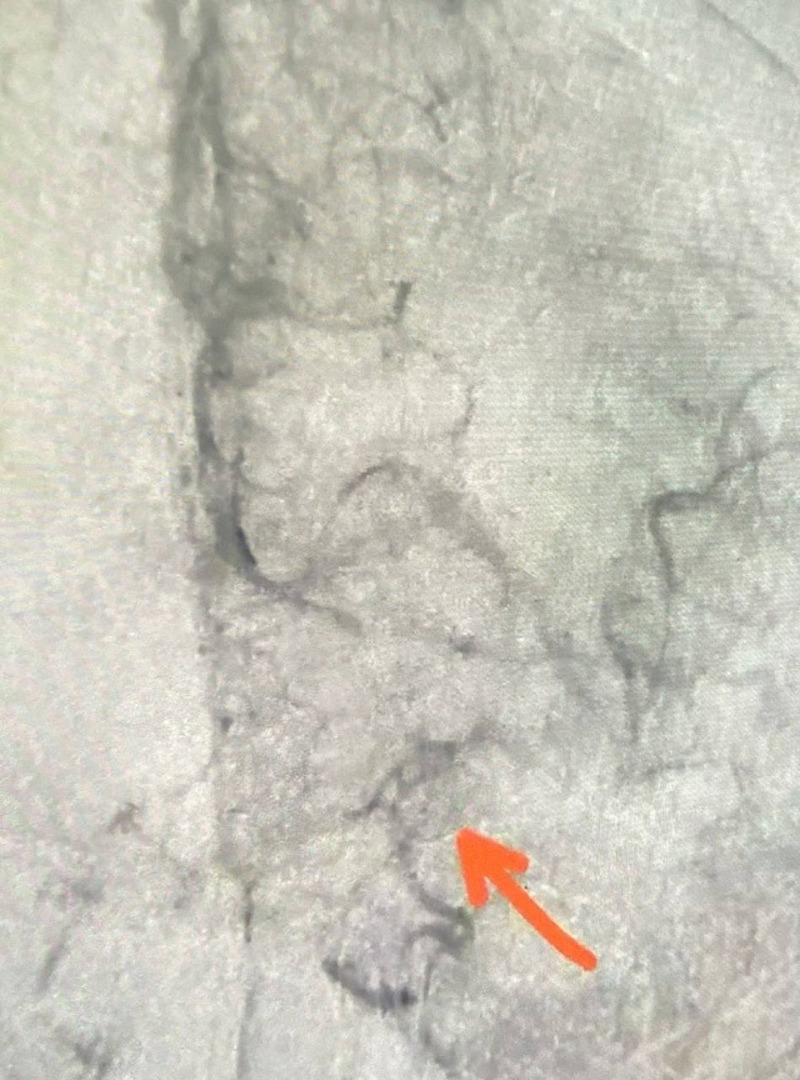

Врачи провели тромболитическую терапию и убрали тромб из мозговой артерии. Уже на операционном столе пациентка стала реагировать на действия медиков и обращённую к ней речь.